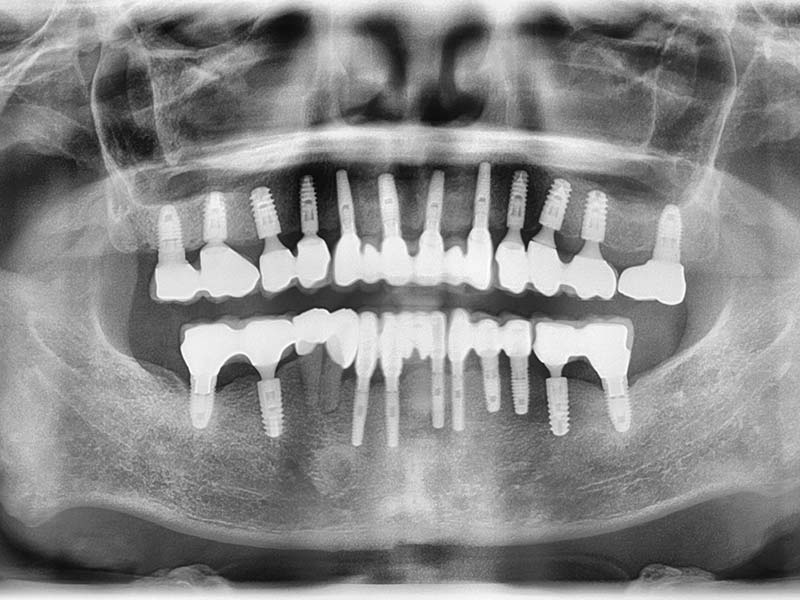

治療前

治療後